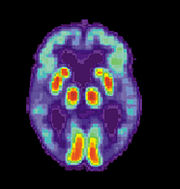

Increasingly, the functional neuroimaging modalities of single photon emission computed tomography (SPECT) and positron emission tomography (PET) are being used to diagnose Alzheimer's, as they have shown similar ability to diagnose Alzheimer's disease as methods involving mental status examination. Furthermore, the ability of SPECT to differentiate Alzheimer's disease from other possible causes, in a patient already known to be suffering from dementia, appears to be superior to attempts to differentiate the cause of dementia cause by mental testing and history. A new technique known as "PiB PET" has been developed for directly and clearly imaging beta-amyloid deposits in vivo using a contrasting tracer that binds selectively to the Abeta deposits. Another recent objective marker of the disease is the analysis of cerebrospinal fluid for amyloid beta or tau proteins. Both advances (neuroimaging and cerebrospinal fluid analysis) have led to the proposal of new diagnostic criteria.